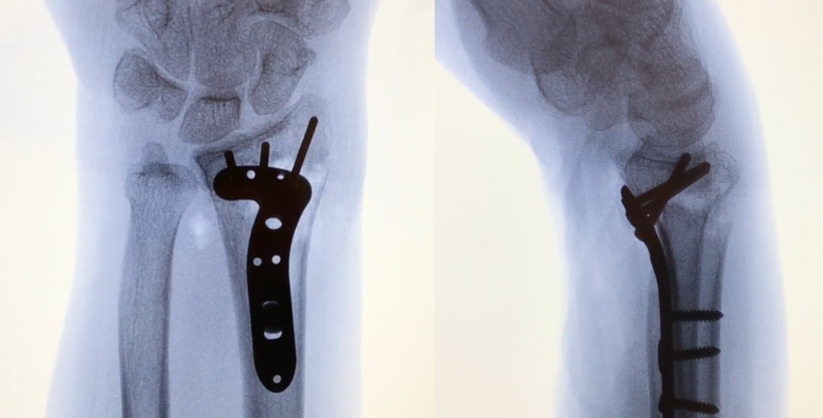

Once the fracture is reduced, a volar plate is placed along the shaft with adequate positioning and fit confirmed under fluoroscopy. The plate is applied to either the proximal or distal fragments first, depending on fracture characteristics and surgeon preference. With affixing to the radial shaft first, a screw is drilled through the oblong hole. The plate may be repositioned in the axial plane if needed before placing the distal screws. Alternatively, the distal fragment can be affixed to the plate first. The plate is then levered to the radius, whereby the volar tilt is corrected through the anatomic shape of the plate. The final plate and screw placement are confirmed using fluoroscopy [Figure 2]. Pearls and Pitfalls are addressed in [Table 1].